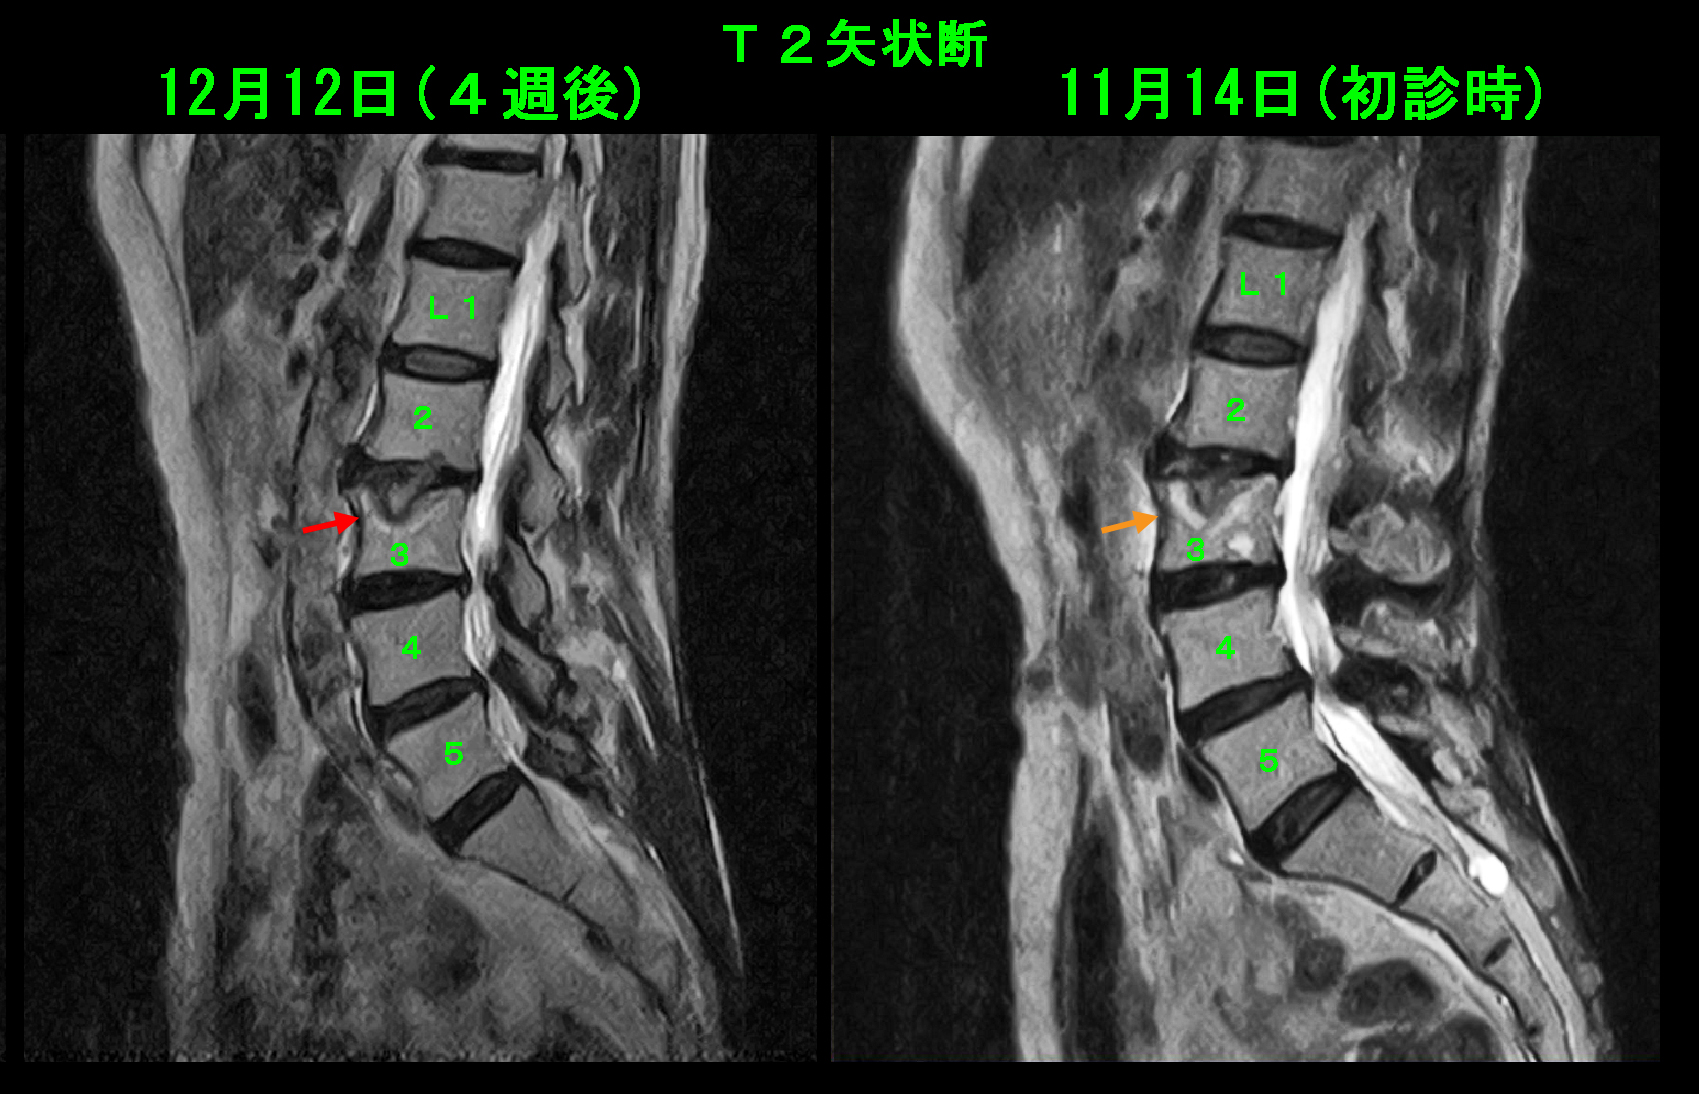

73才女 MR2.jpg

8週後のMRI再検査の画像を提示します。T2矢状断ではL3椎体の高輝度所見は軽減化しており、上縁の皮質骨の黒い線が認識可能となっています。これは壊れたL3の上縁の皮質骨が修復されたことを意味しています。

73才女 MR3.jpg

T1矢状断も同様であり、低輝度所見領域は縮小しており、上縁の皮質骨のラインが明瞭かしています。8週間の運動休止の後にエアロビクスとヨガを再開しました。この患者さんはその後しばらく通院されましたが、腰痛の訴えは再発しませんでした。